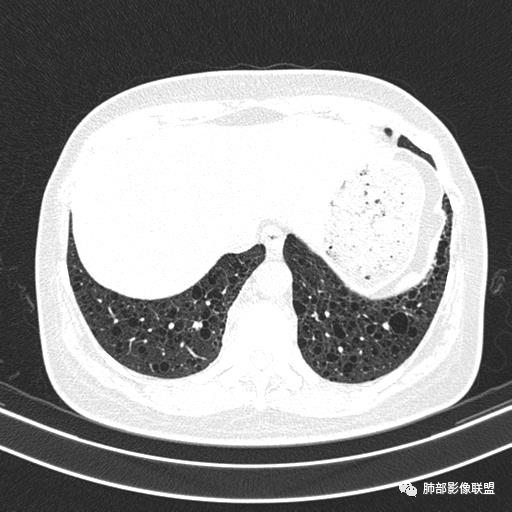

中年女性,不吸烟

双肺弥漫囊腔,累及肋膈角,囊腔形态相对规则单一。

符合LAM

CT平扫示双肺弥漫分布大小不等囊状薄壁透光区,无内、中、外带分布差异,间质稍示增厚。拟LAM

我也支持刘老师。中年女性,咳嗽气喘,有苯吸入史,双肺野多发囊腔,囊腔形态相对规则,大小不一,壁薄,有的似无壁,双肺弥漫磨玻璃影,有间质性改变,育龄期女性,首选考虑lam,但是患者有吸入苯病史半年,囊腔形态不是很规则,大小不一,分布不均匀,有的无壁似小叶中央肺气肿,有弥漫性磨玻璃及间质性改变,不排除吸入引起的间质性肺炎?

中年女性,双肺弥漫性磨玻璃密度影,并见弥漫性分布大小不一囊腔,壁薄,形态规则,考虑lam,鉴别苯中毒肺损伤致间质改变

中年女性育龄期妇女,咳嗽气喘,无吸烟史,有苯吸入史。影像:双肺弥漫均匀小囊腔,无明显分布优势,囊腔形态欠规则,壁薄,部分囊腔边缘血管征,伴双肺弥漫磨玻璃影,无结节,考虑lam,鉴别苯中毒肺损伤,囊腔多有分布优势,小叶中心分布为主,形态规整等

中年女性,两肺弥漫分布囊性低密度影,壁薄,相对规则,境界尚清晰,考虑LAM

中年育龄期女性,双肺多发含气囊腔弥漫性分布,囊间肺组织结构正常,常规考虑Lam

女,46,活动性气喘1年。苯吸入史半年。胸部CT:两肺弥漫囊腔,上至肺尖,下至肋膈角,形态类似小囊腔。考虑:LAM,鉴别LIP,BHD,PLCH等。

双肺弥漫大小不一薄壁含气囊腔,囊间肺组织正常,正常肺背景,肺尖肺底受累;青年女性,气喘,支持LAM

双肺多发大小相近的囊状影,分布趋势趋于一致,中年女性,考虑LAM。部分囊内见血管及分隔影,小叶中心性肺气肿代排

CT表现:双肺弥漫大小不等的薄壁囊腔,囊壁<2mm,外形规则,血管影多位于囊腔周围,囊腔之间肺组织正常,随着疾病进展到晚期,囊腔变大、增多,不可胜数,囊腔可融合成较大的囊,与肺气肿相似,形成间质性肺纤维化。部分病例可出现结节影。